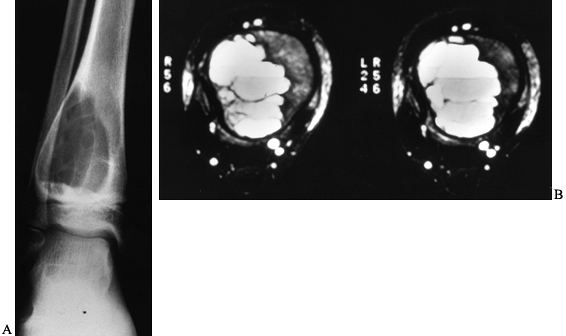

stage 3 disease. The radiographic appearance of an ABC is quite

distinctive and almost diagnostic (Fig. 127.8A).

The characteristic features include a subperiosteal lytic expansile

lesion inflating and thinning the cortex. In the early stages,

periosteal reaction is scarce, giving the appearance of a malignant

tumor. The lesion typically involves the metaphysis, and occasionally

the epiphysis, and it may even cross the physis. Because the periosteal

response may extend along the shaft of the bone beyond the lesion, it

may have the appearance of a finger in a balloon. Most often the lesion

is eccentric, but it can be central. In the

spine,

the lesion typically involves the posterior elements but may expand to

involve the vertebral body as well as adjacent vertebrae. CT and MRI

are useful imaging modalities, especially in the axial skeleton. They

are particularly helpful in confirming the diagnosis by demonstrating

the characteristic fluid levels within the cyst (Fig. 127.8B).

It should be stressed, however, that the presence of these fluid–fluid

levels is not pathognomonic for ABC. Other lesions, including GCT,

unicameral bone cyst with fracture, and osteosarcoma, may have this

finding.

![]() |

|

Figure 127.8. A:

AP radiograph of an aneurysmal bone cyst (ABC) shows an expanded radiolucent lesion in the metaphysis of the right distal tibia. The periosteum is intact and well marginated. There are some internal septations within the lesion. B: An MRI of this lesion shows the classic fluid–fluid levels. This was biopsied and proved to be an ABC. |